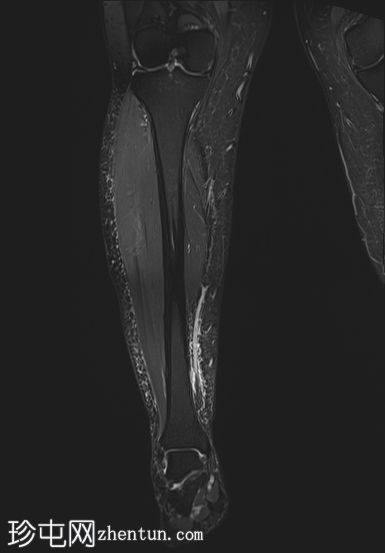

冠状位

STIR序列

PD/STIR序列显示肌腱交界处附近前侧肌纤维局灶性异常高信号,符合部分肌腱拉伤/撕裂。腓肠肌内侧头与下方比目鱼肌之间可见一条细小的液性裂隙,向上延伸——典型的网球腿表现。邻近肌间筋膜间隙轻度水肿。未见全层肌肉撕裂或肌腱回缩。未见血肿或积液。腓肠肌外侧头、比目鱼肌及其余小腿肌肉信号和体积均正常。所见骨骼未见异常。